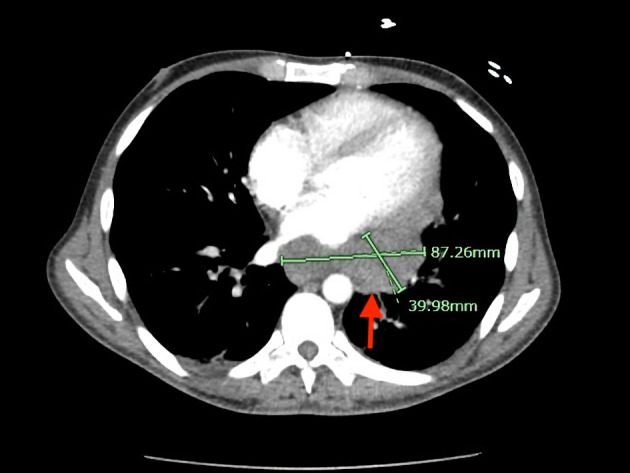

原发性积液性淋巴瘤(PEL)是一种罕见的、侵袭性的大b细胞淋巴瘤变体,它总是与人类疱疹病毒8 (HHV8)相关,主要发生在人类免疫缺陷病毒(HIV)感染的患者中,其致瘤性通常因同时感染eb病毒而增强。它通常表现为体腔内的浆液积液,没有可检测到的实体瘤。PEL的腔外变异可能是一个诊断挑战。一名37岁男性HIV/ AIDS患者被转至我院接受纵隔肿块检查,诊断为嗜血球性淋巴组织细胞增多症(HLH)、发热、全血细胞减少症、肝脾肿大、腹膜后淋巴结病和耗损综合征。增强计算机断层扫描显示一大块软组织肿块沿中/后纵隔延伸至左肺门,左侧胸腔积液大量。内镜下细针活检显示大的多形性淋巴瘤细胞片,核仁突出,细胞质丰富。这些细胞在胸膜液细胞自旋涂片上也可见。免疫组化染色显示淋巴瘤细胞CD3(小亚群)、CD45、CD138、MUM-1和HHV8阳性,CD5、CD20、CD30、ALK1、AE1/3和PAX-5阴性。淋巴瘤细胞eb病毒编码RNA(原位杂交)也呈阳性。腔外PEL中的实性肿块已被证明累及淋巴结和/或实体器官,如胃肠道、肺、肝、脾和皮肤,其表型与典型PEL相似,只是它们可能表达CD45表达较低的b细胞标记物和/或t细胞抗原的异常共表达。本病例显示了不同寻常的PEL表现为纵隔肿块伴HLH。

Primary effusion lymphoma (PEL) is a rare, aggressive large B-cell lymphoma variant that is invariably associated with human herpesvirus 8 (HHV8), predominantly in human immunodeficiency virus (HIV)-infected patients, and its oncogenicity is often augmented by coinfection with Epstein-Barr virus. It typically presents as a serous effusion in body cavities without detectable solid tumors. The extracavitary variant of PEL may represent a diagnostic challenge. A 37-year-old man with HIV/acquired immunodeficiency syndrome (AIDS) was transferred to our hospital for evaluation of a mediastinal mass with associated clinically diagnosed hemophagocytic lymphohistiocytosis (HLH), fever, pancytopenia, hepatosplenomegaly, retroperitoneal lymphadenopathy, and wasting syndrome. Contrast-enhanced computed tomography showed a large soft tissue mass extending along the middle/posterior mediastinum into the left hilum and a large left pleural effusion. Endoscopic fine-needle biopsy of the lesion showed sheets of large pleomorphic lymphoma cells with prominent nucleoli and abundant cytoplasm. These cells were also seen on the cytospin smear of pleural fluid. Immunohistochemical stains showed lymphoma cells positive for CD3 (small subset), CD45, CD138, MUM-1, and HHV8 and negative for CD5, CD20, CD30, ALK1, AE1/3, and PAX-5. The lymphoma cells were also positive for Epstein-Barr virus-encoded RNA (EBER) (in situ hybridization). Solid masses in extracavitary PEL have been shown to involve lymph nodes and/or solid organs such as the gastrointestinal tract, lung, liver, spleen, and skin, with a similar phenotype as classic PEL except that they may express B-cell markers with lower expression of CD45 and/or aberrant coexpression of T-cell antigens. This case illustrates the unusual manifestation of PEL as a mediastinal mass with associated HLH.